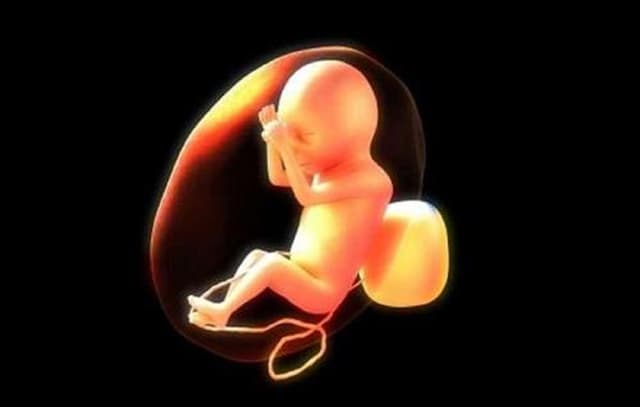

Những điều cần biết về tràn dịch màng phổi thai nhi

Tràn dịch màng phổi thai nhi là một trong những bất thường có thể xuất hiện trong lúc bào thai đang tăng trưởng. Tràn dịch màng phổi nặng có thể làm phổi kém phát triển (thiểu sản phổi) hoặc gây suy tim. Phát hiện sớm tràn dịch màng phổi và có biện pháp xử lý […]